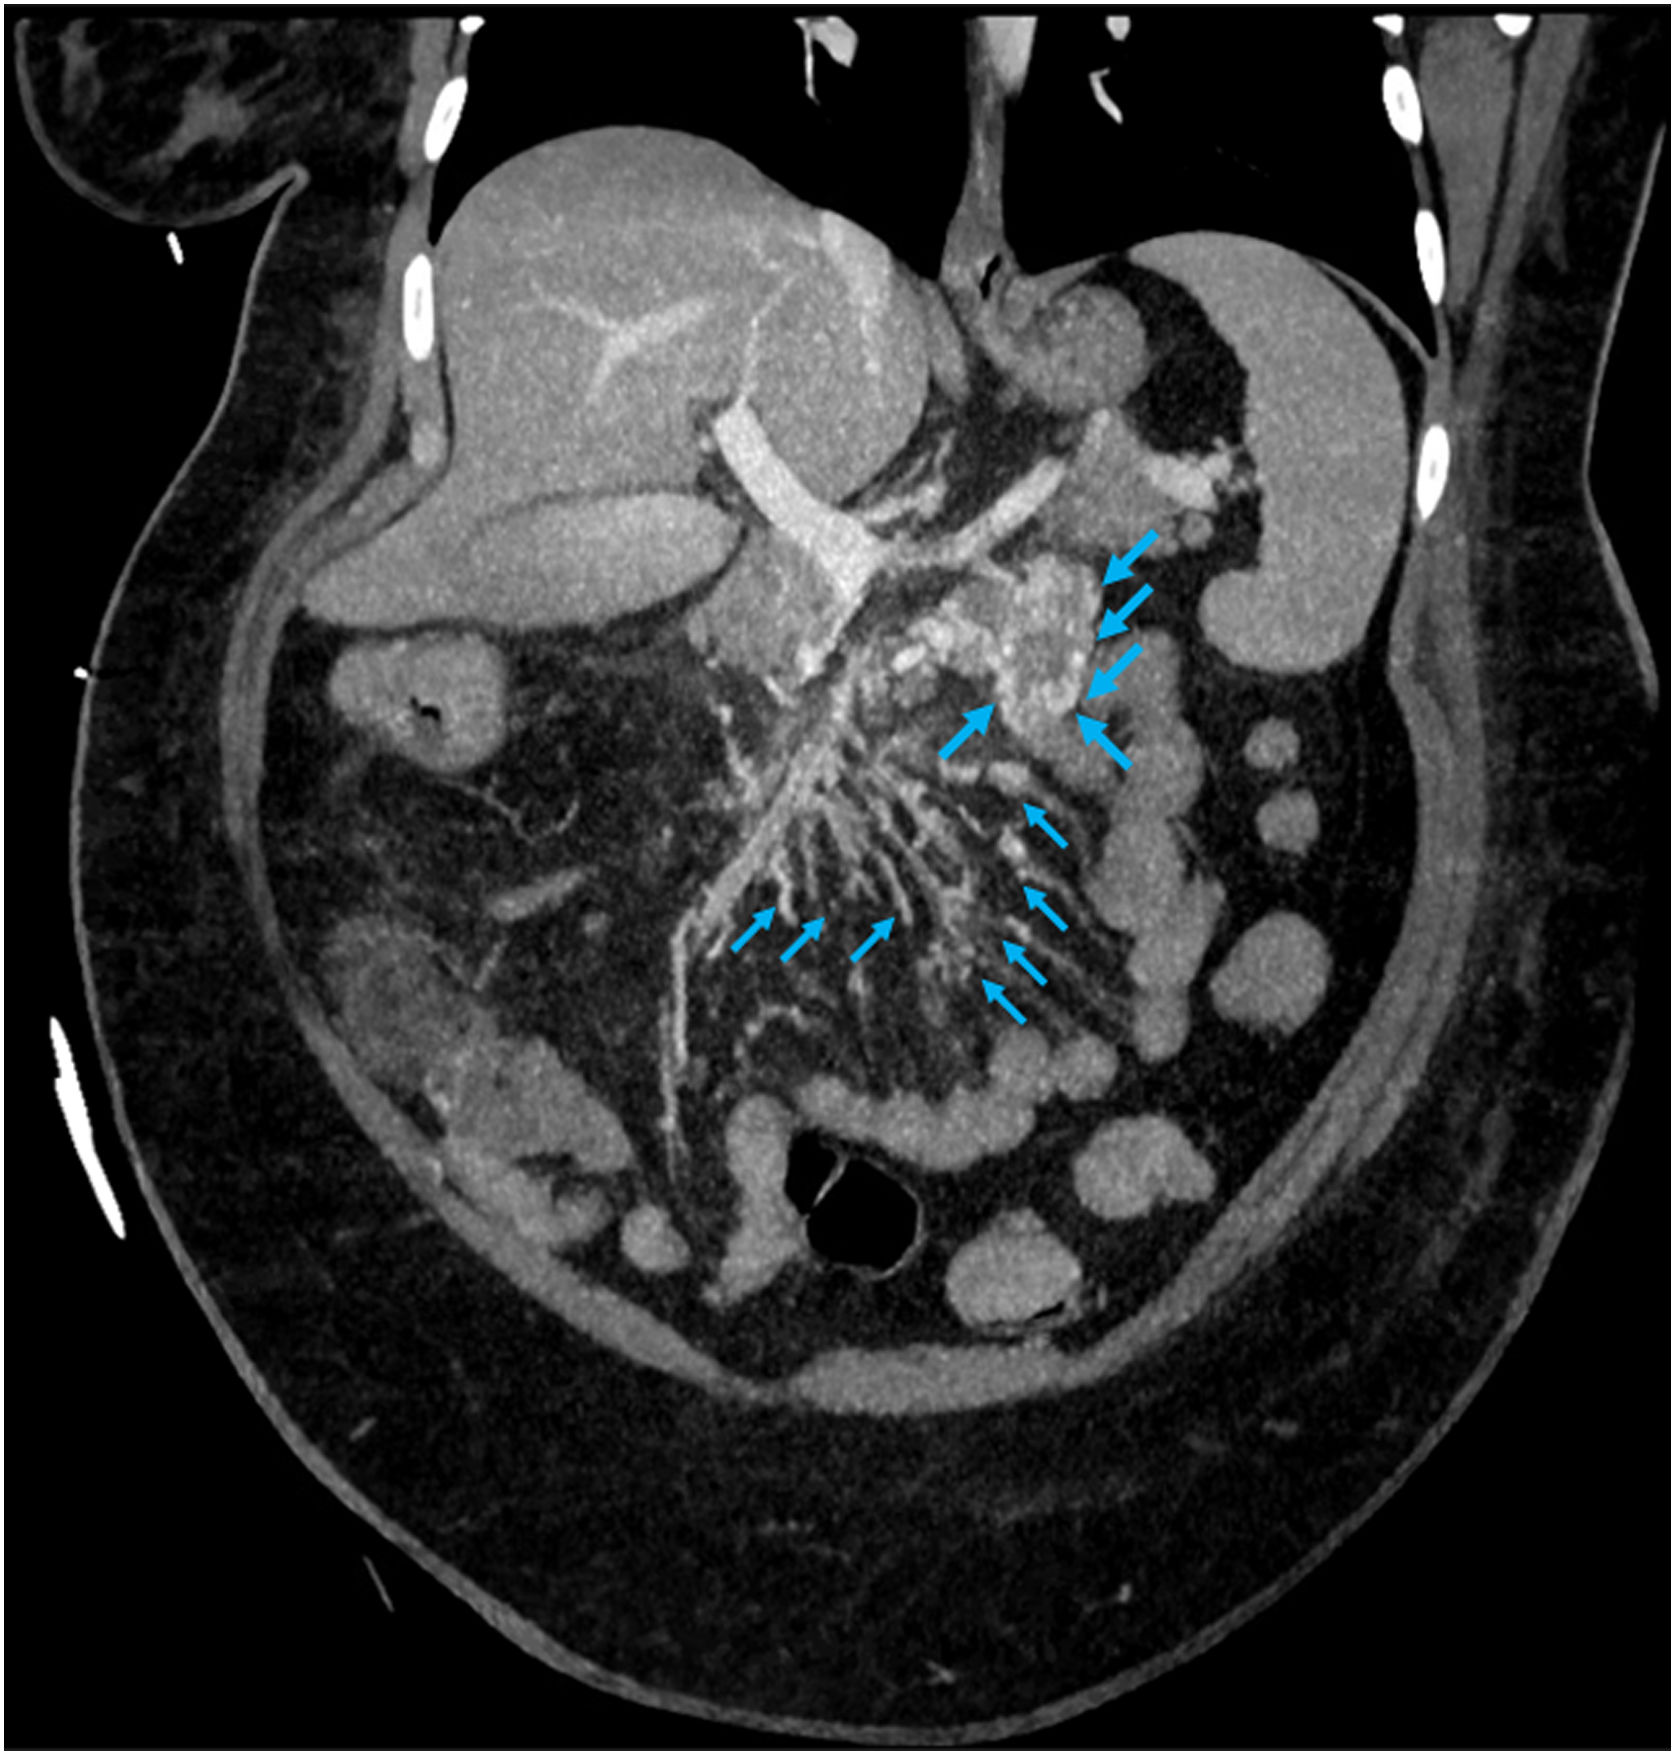

Mujer de 41 años con antecedentes de obesidad y aborto espontáneo, que ingresa en UCI por rectorragias y anemización con nulo rendimiento transfusional. Se realizan colonoscopia y gastroscopia, sin objetivar punto de sangrado, pero sí restos hemáticos frescos. La tomografía muestra abundantes varices de yeyuno proximal (fig. 1), compatible con hipertensión portal, secundaria a trombosis crónica de la vena mesentérica superior (fig. 2).